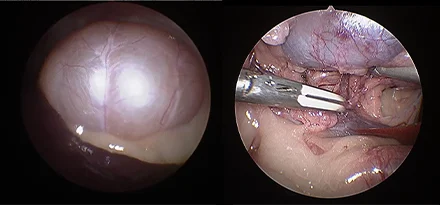

복강경

기존의 개복수술은 충분한 노출을 위하여 복부의 피부와 복벽 근육을 길게 절개해야 합니다.

하지만 복강경을 이용하면 보통 3mm-10mm 직경의 포트를 통해 복강 내에 이산화탄소를 주입하여 공간을 만들고,

카메라를 통해 더 뚜렷하게 시각화할 수 있고 지혈 기구를 통해 장기들을 안전하게 분리하여 절제할 수 있습니다.

복강경의 경우 대형견에서 그 장점이 뚜렷하며 현재는 소형견, 고양이에서도 이러한 장점 때문에 최소 침습 수술을 진행하게 됩니다.

본원에서는 간단한 중성화나 조직생검 외에도 부신절제술, 담낭절제술, 신장절제술, 비장절제술, 간엽절제술 등을 포함한

고난도 수술도 실시합니다.

복강경신장절제술

복강경부신절제술

복강경담낭절제술

* 리본동물의료센터 케이스 사진으로 무단 복제 및 도용을 금지합니다.